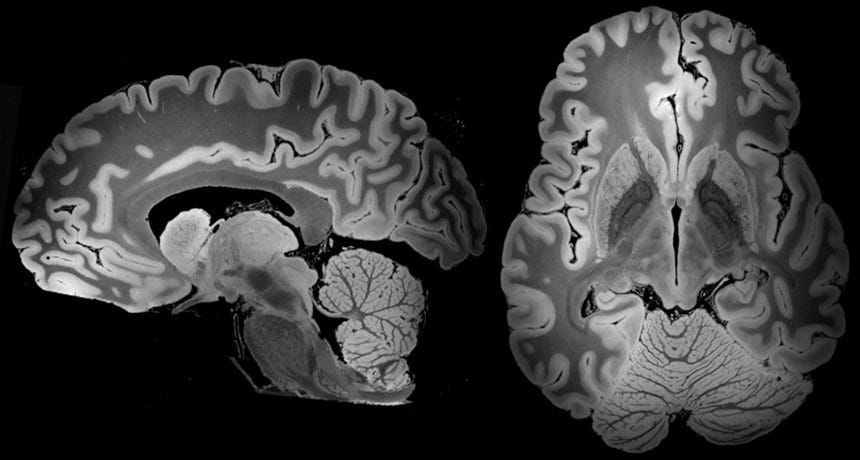

Diagnosing a brain tumor begins with Magnetic Resonance Imaging (MRI). Once MRI shows that there is a tumor in the brain, the most regular way to infer the type of brain tumor is to glance at the results from a sample of tissue after a biopsy/surgery.

An MRI uses magnetic fields, to produce accurate images of the body organs. It can be used to measure the tumor’s size. A special dye called a contrast medium is given before the scan to create an accurate snd clearer picture. This dye can be injected into a patient’s vein or given as a pill or liquid.

MRIs create more accurate snd clearer pictures than CT scans and are the favored way to diagnose a brain tumor. The MRI may be of the brain, spinal cord, or both, depending on the type of tumor presumed and the plausibility that it will spread in the CNS. There are different types of MRIs and the results of a neuro-test, done by the neurologist, help determine which type of MRI to use.